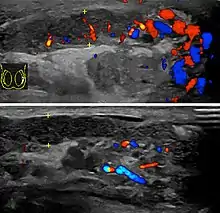

Doppler ultrasound of epididymitis, seen as a substantial increase in blood flow in the left epididymis (top image), while it is normal in the right (bottom image). The thickness of the epididymis (between yellow crosses) is only slightly increased.

Diagnosis is typically based on symptoms.[1] Conditions that may result in similar symptoms include testicular torsion, inguinal hernia, and testicular cancer.[1] Ultrasound can be useful if the diagnosis is unclear.[1]

Epididymitis usually has a gradual onset. Typical findings are redness, warmth and swelling of the scrotum, with tenderness behind the testicle, away from the middle (this is the normal position of the epididymis relative to the testicle). The cremasteric reflex (elevation of the testicle in response to stroking the upper inner thigh) remains normal.[1] This is a useful sign to distinguish it from testicular torsion. If there is pain relieved by elevation of the testicle, this is called Prehn's sign[11]

Before the advent of sophisticated medical imaging techniques, surgical exploration was the standard of care. Today, Doppler ultrasound is a common test: it can demonstrate areas of blood flow and can distinguish clearly between epididymitis and torsion. However, as torsion and other sources of testicular pain can often be determined by palpation alone, some studies have suggested that the only real benefit of an ultrasound is to assure the person that they do not have testicular cancer.[12]:p.237 Nuclear testicular blood flow testing may be used.[13]